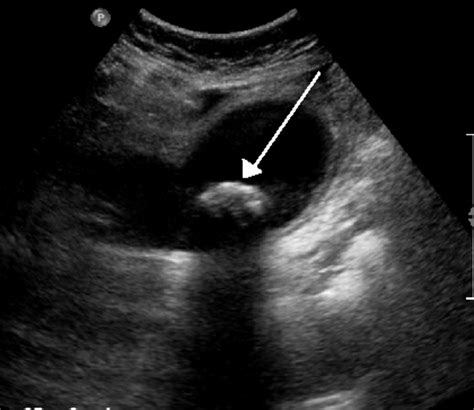

The primary advantage of using an ultrasound for gallbladder problems is its unmatched ability to identify gallstones. Because gallstones are often calcified or dense, they reflect sound waves differently than the surrounding fluid-filled gallbladder, making them clearly visible on the monitor. Furthermore, ultrasound is highly efficient at detecting signs of inflammation, such as a thickened gallbladder wall or the presence of fluid around the organ, which are indicators of cholecystitis.

Cholelithiasis (Gallstones) Highly reflective (echogenic) spots within the gallbladder, usually with a characteristic "acoustic shadow" behind them.

Polyps Small, non-mobile growths attached to the wall of the gallbladder that do not cast a shadow.